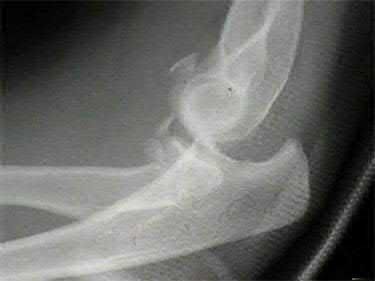

Question 15

Following a traumatic knee injury, a 24-year-old athlete undergoes an arthroscopic meniscal repair. Which zone of the meniscus has the highest healing potential, and from which vessels does it derive its primary blood supply?

Explanation

The peripheral 10% to 30% of the meniscus (the red-red zone) is well-vascularized and thus has the highest healing potential. The blood supply to this peripheral zone is derived from the capsular and synovial branches of the medial and lateral, superior and inferior geniculate arteries. The central white-white zone is avascular and relies on diffusion from synovial fluid, lacking the intrinsic capacity to heal.